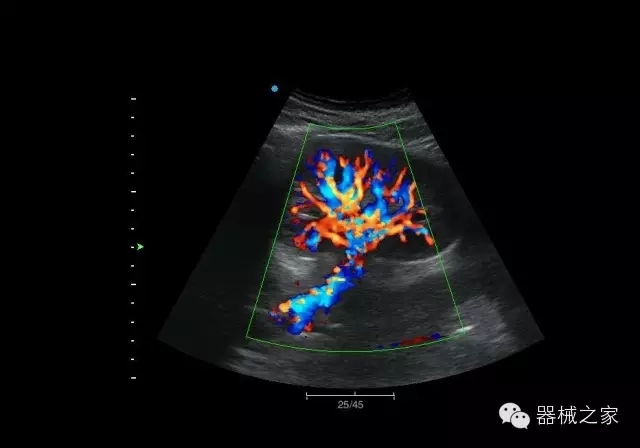

睪丸低速血流

臍帶血流